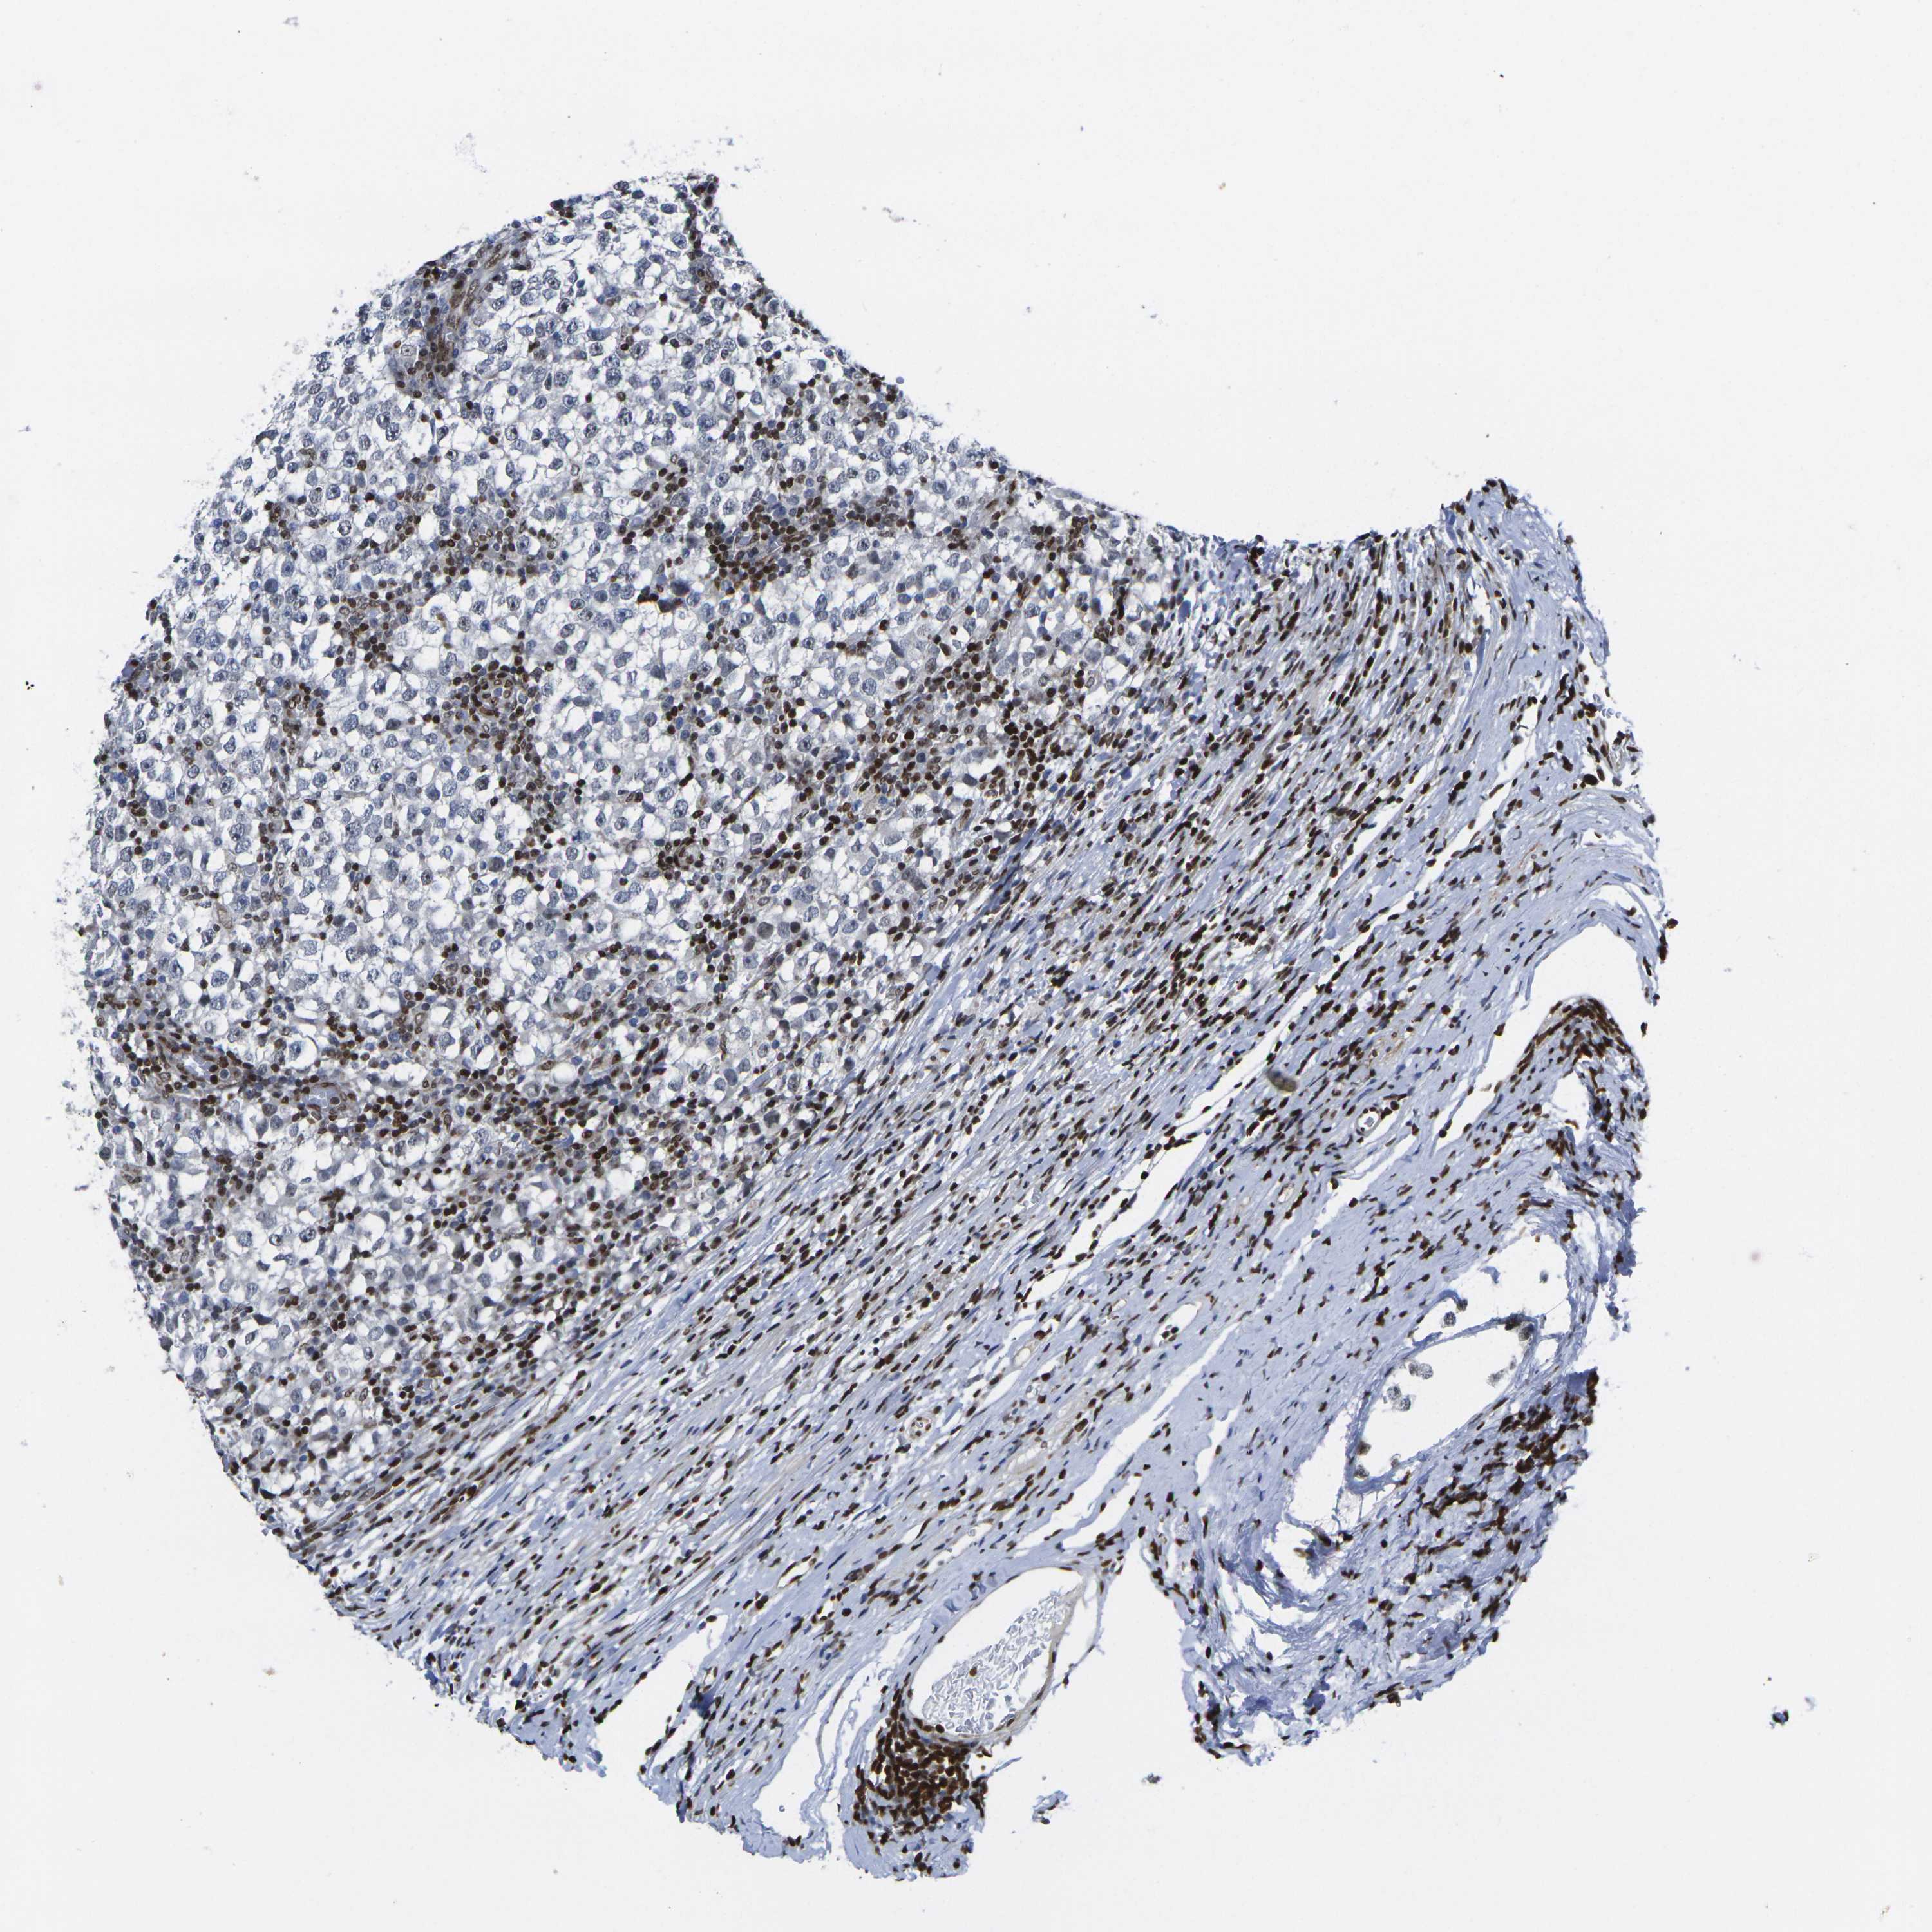

TESTIS CANCER - Protein expressioni

A mouse-over function shows sample information and annotation data. Click on an image to view it in a full screen mode. Samples can be filtered based on level of antibody staining by selecting one or several of the following categories: high, medium, low and not detected. The assay and annotation is described here.

Note that samples used for immunohistochemistry by the Human Protein Atlas do not correspond to samples in the TCGA dataset.

Antibody stainingi

Antibody staining in the annotated cell types in the current human tissue is reported as not detected, low, medium, or high, based on conventional immunohistochemistry profiling in selected tissues. This score is based on the combination of the staining intensity and fraction of stained cells.

Each image is clickable and will lead to virtual microscopy that enables deeper exploration of all samples and also displays staining intensity scores, fraction scores and subcellular localization as well as patient and tissue information for each sample.

Antibody HPA068431

Antibody CAB012235

Staining

High

Medium

Low

Not detected

Intensity

Strong

Moderate

Weak

Negative

Quantity

>75%

75%-25%

<25%

None

Location

Nuclear

Cytoplasmic/membranous

Cytoplasmic/membranous,nuclear

Seminoma, NOS

Carcinoma, Embryonal, NOS